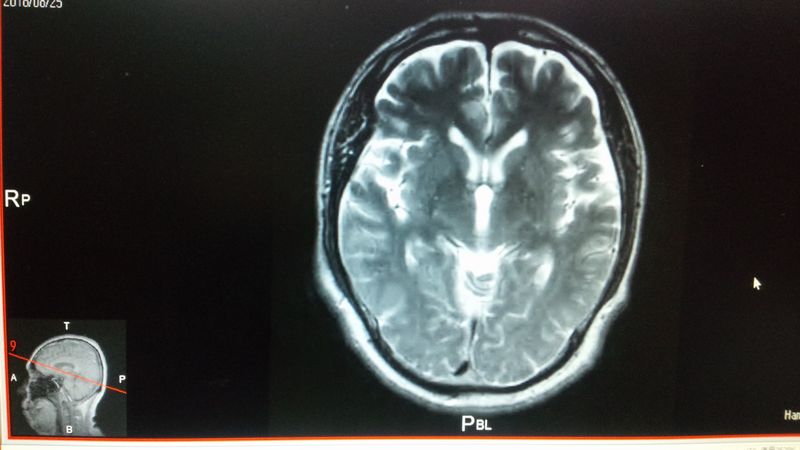

それから、今回びっくりしたのが、脳ドックのMRI結果として、DVDが付いてきた。

「パソコンで見る事が出来るのかな?」と入れてみると、DVDに起動ソフトも入っている様で、病院で見たデータが・・・。

送られてきたDVDの中のデーターの一例

左下の赤線の断面図が、拡大され、マウスを回すと、その断面図が次々に展開される仕組み。

今回の結果では、脳梗塞等の異常は、見つからなかったとの見解を貰ったのだが、脳の周りの隙間が多くないかな?

振ると「カランカラン」と音がしそう?